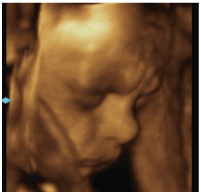

4Dエコーとは、3Dエコーに時間の要素を加えたものです。従来の2Dエコーでは断面的にしか見えなかった赤ちゃんの画像が、4Dエコーを導入してからはリアルタイムで動画として抽出できるようになりました。

週数によってお腹の中の赤ちゃんの顔や手足の様子がはっきりとわかります。

4Dエコーで見た胎児の様子。

当院設置の4D映像です。